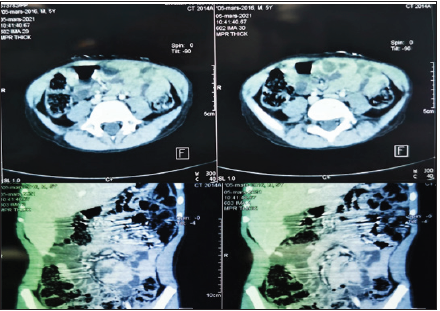

Figure 1:CT image showing a multi-compartmental mass between the digestive loops.

A multitude of clinical diagnoses, both medical and surgical,

have been mentioned. The laboratory tests were normal. X-ray

examinations were performed to support the etiological diagnosis.

An ASP was carried out without anomalies. Abdominal ultrasound,

coupled with Doppler, showed a cystic, multi-compartmental mass

of the right iliac fossa, devoid of vascularity, with normally located

mesenteric vessels. Abdominal tomodensitometry objectified the

presence of a voluminous oblong formation, mesenteric, attached

to the cecal wall and to the right colon, insinuating between the

digestive structures without pushing them back, of fluid density

without clean wall, not enhanced after injection of the product.

of contrast; first suspecting a cystic lymphangioma (Figure 1). We